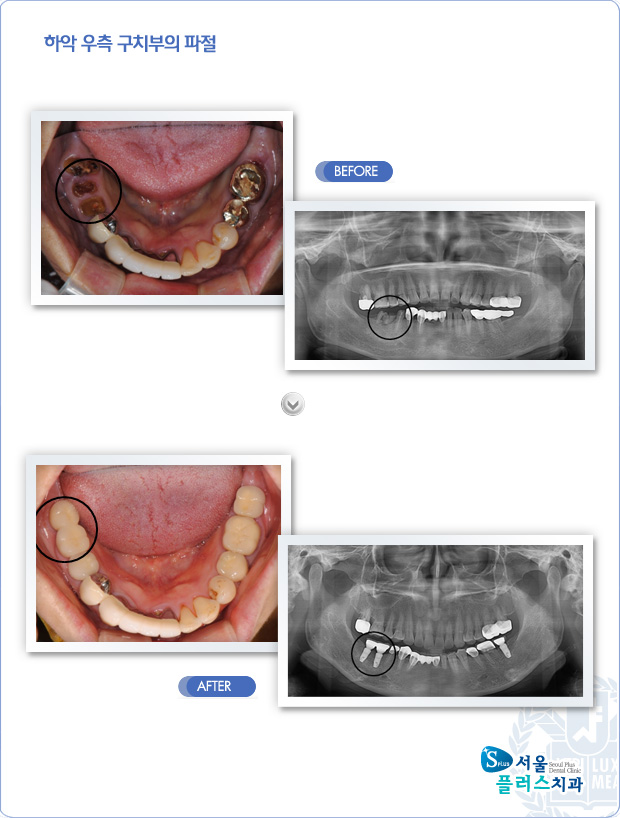

[임플란트] 하악 우측 구치부의 파절